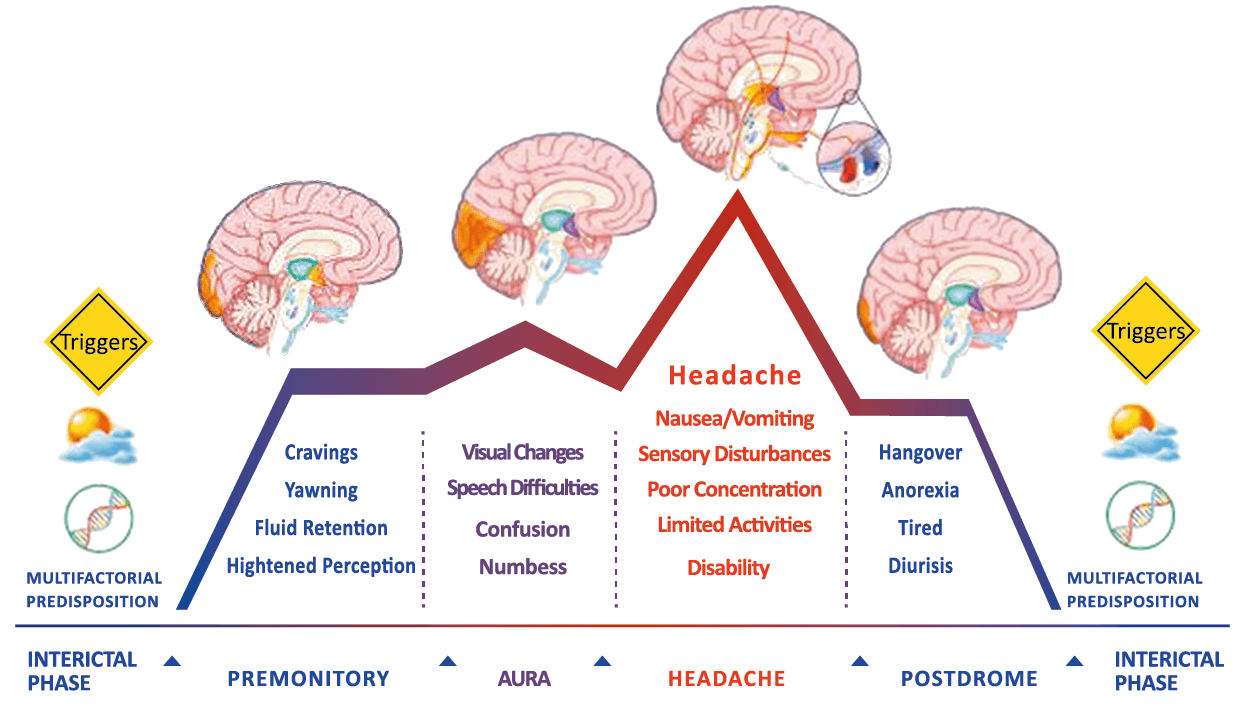

Todo lo mencionado contribuye al fenotipo del migrañoso y son vías que continuamente se están explorando para el desarrollo de nuevas terapias agudas y preventivas del dolor, más seguras y eficaces. Sin embargo, existe una controversia que gira en torno a dos cuestiones: la iniciación y el origen del dolor además de que todavía no se conoce el origen de los mecanismos neuronales que subyacen a la condición primaria en las personas susceptibles. Definitivamente la migraña implica la activación y sensibilización de las vías trigeminovasculares, así como el tronco cerebral y los núcleos diencefálicos(88). La vía aferente comienza en las aferentes vasculares nociceptivas de la duramadre que están para advertir, no para localizar. Su proyección al tálamo y la corteza y como se regula esta vía en cada nivel y por múltiples sistemas, ofrece la posibilidad de comprender los síntomas complejos y orientar las terapias. Los ataques comienzan como síntomas premonitorios, dificultad para concentrarse, bostezos, fluctuaciones del humor; y cambios homeostáticos, como la alimentación y el equilibrio de líquidos, que pueden incluir sensibilidades más generalizadas, como fotofobia y fonofobia. La fase premonitoria da paso a la fase de dolor con el sufrimiento acompañante y termina en una fase posdrómica de sentirse agotado por la experiencia. (Figura 1)

En la primera fase (figura 3), premonitoria, que precede a la cefalea, los sistemas del tronco encefálico y diencefálico modulan las señales aferentes, la fotofobia a la luz o la fonofobia al sonido, comienzan a disfuncionalizarse y eventualmente a evolucionar a la fase de dolor y con el tiempo a la fase de resolución o posdrómica. Aproximadamente en un tercio de los pacientes con migraña, sus ataques están asociados con déficits neurológicos, que incluyen perturbaciones corticales, denominadas colectivamente aura de migraña(3).

Se cree que esta activación secuencial explica la naturaleza pulsátil del dolor en la migraña, la hipersensibilidad sensorial nociceptiva, los síntomas neurológicos asociados que incluyen náuseas, vómitos, alteración de la alimentación y el sueño, así como la alteración cognitiva. Clínicamente, sin embargo, hay muchas lagunas. Los síntomas premonitorios en la migraña pueden estar presentes 24 a 48 h antes del dolor de cabeza y están representados por cambios en la activación en las regiones del cerebro medio e hipotalámico. Los desencadenantes de la migraña, como la privación de sueño y alimentos y el estrés, están bajo control homeostático.

El dolor de la migraña es, sin duda, una consecuencia de la activación o la percepción de la activación de los mecanismos neurovasculares, de allí que sea considerado un trastorno puramente neuronal. Mucha evidencia indica que los cerebros de las personas con migraña pueden ser diferentes en la forma en la cual responden a la estimulación sensorial, incluso interictalmente(102). Una hipótesis alternativa y que lo abarca todo es que el cerebro está en el centro del desencadenamiento de la migraña. Más que una activación secuencial de diferentes regiones del cerebro, la migraña es un trastorno del cerebro y por lo tanto, se considera un “estado cerebral”, que es una consecuencia de cambios o disfunciones en las regiones del tronco encefálico y el hipotálamo, que contribuyen a su vez a cambios a nivel celular y vascular en muchas regiones del cerebro. Esta hipótesis establece que la migraña puede describirse mejor como una consecuencia de la disfunción en el tronco encefálico y los núcleos hipotalámicos que normalmente modulan o activan las entradas sensoriales, como el tacto, la luz, los sonidos y los olores. Estos núcleos del tronco encefálico y del hipotálamo pueden considerarse “mediadores de la migraña” y su disfunción puede llevar al fracaso de los mecanismos de integración y filtrado cerebrales, lo que da como resultado la percepción de activación de los sistemas sensoriales en condiciones normales. La compleja red de conexiones entre las regiones del tronco encefálico, que incluyen PAG, RVM, locus ceruleus y SuS y los núcleos diencefálicos, incluidos el hipotálamo, el tálamo y la corteza, pueden conducir a la generación de síntomas a través de la misma disfunción central. La disfunción en estas regiones, a través del control descendente del tráfico nociceptivo trigeminovascular, puede conducir a la percepción del dolor de cabeza a través de la palpitación de los vasos normales y la disfunción continua puede conducir a la sensibilización central de las neuronas trigeminovasculares y la exacerbación del dolor con la actividad física normal, así como en la piel: alodinia cefálica y extracefálica. La convergencia de entradas sensoriales en el tálamo que se proyectan a la corteza puede explicar la hipersensibilidad a la luz, los sonidos y los olores. La misma disfunción puede conducir a cambios homeostáticos, controlados por el hipotálamo, relacionados con el sueño, la alimentación y la actividad. La alteración general de la función cortical y subcortical puede desencadenar eventos como el aura migrañosa y extenderse a una incapacidad general para funcionar correctamente. Los factores genéticos heredados juegan claramente un papel en la predisposición a la susceptibilidad a la migraña, al igual que el papel de los desencadenantes potenciales de la migraña, cuyo vínculo común parece jugar en el corazón de la homeostasis cerebral en el hipotálamo y el tronco encefálico. (figura 7).